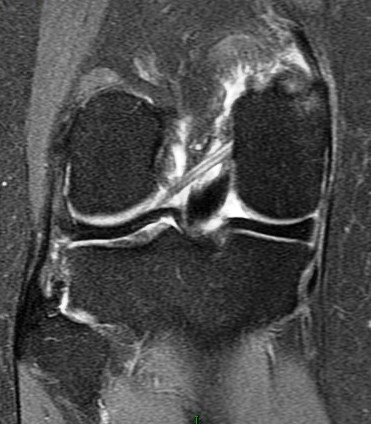

Figure 3 for case Partial tear of the tendon of the medial head of the gastrocnemius muscle ( RID2921 )

Figure 3